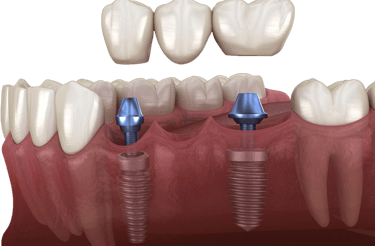

Implant-Supported Bridge

Implant-Supported Bridge: Connected to dental implants – strong and long-lasting.